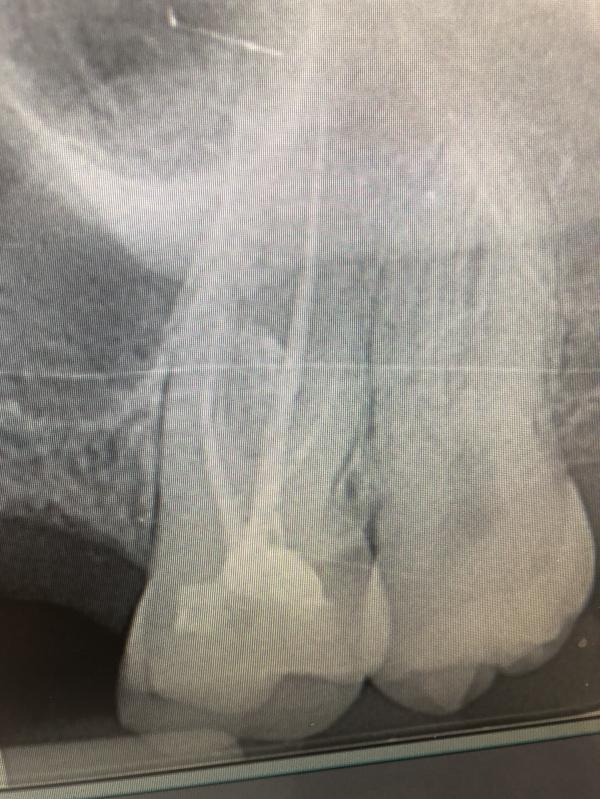

Заболел мне опять зуб.. не знаю, может от нервов.. пошла я сегодня здесь опять к врачу.. он хотел его сразу рвать.. или опять что-то там с корнями делать (тут это стоит более 1000 евро) думаю, нееее нихрена.. встала в общем и ушла.. скидываю снимок своему зубному опять в Одессу 😂😂😂🤦🏻♀️ Он ржёт с меня и отвечает, хорошо, что ты не побоялась и не позволила.. ничего криминального он вообще не видит, тем более для вырывания зуба. Попить нимесил и должно всё успокоится. Дотянуть до Одессы и если понадоб...